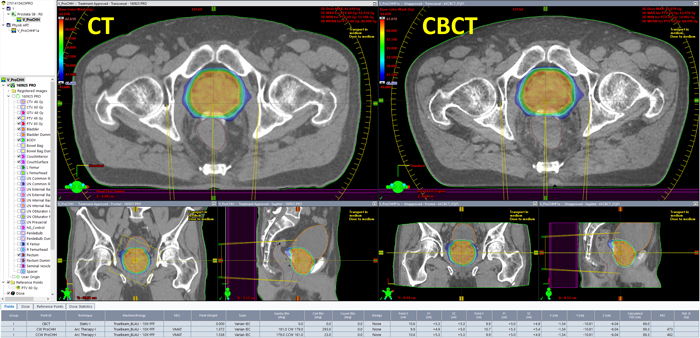

The patient anatomy shown in the first image belongs to a prostate plan with the CHHiP prescription 20 x 3 Gy = 60 Gy to the (central) high dose region, 48 Gy to the periphery. The hydrogel which was used to push the rectum away from the high dose region is also visible.

During the first session, we asked the therapists to aquire a Pelvis scan instead of the Spotlight they would normally choose. During CBCT aquisition, the PerfectPitch couch is always levelled (Pitch = Roll = 0.0°). Then an online match against the planning CT is performed, followed by a 6 DoF couch shift, followed by the treatment.

The elegance of the integrated Varian system is that as soon as the treatment session on the TrueBeam is closed, the CBCT image can be opened on any Eclipse workstation on the network (no export). Immediately after the treatment, we performed the following steps in order to get dose calculated on today's CBCT:

Dose on the CBCT is calculated with the same parameters as in the treatment approved plan (AXB, 2mm grid). Since the patient had no metal implants, we skipped the "Segment High Density Artifacts" step in Contouring. Consequently, no material assignment was necessary.